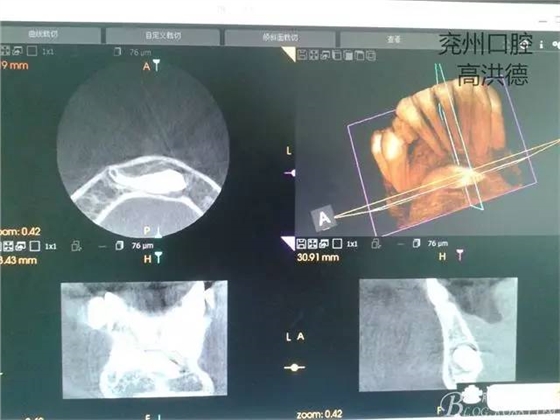

三維成像

矢狀位